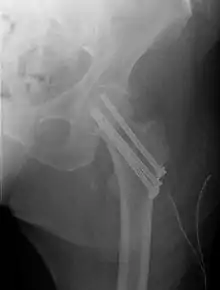

Fracture treated with cannulated screws

For low-grade fractures (Garden types 1 and 2), standard treatment is fixation of the fracture in situ with screws or a sliding screw/plate device. This treatment can also be offered for displaced fractures after the fracture has been reduced.

Fractures managed by closed reduction can possibly be treated by percutaneously inserted screws.[29]